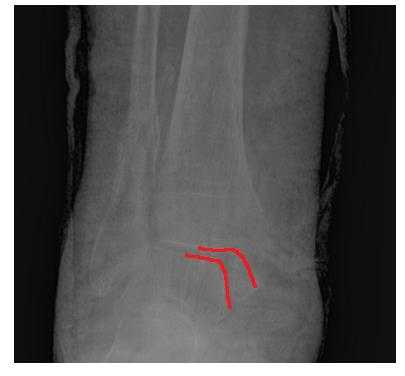

На рентгенограммах в гипсе определяется значительный подвывих таранной кости кнаружи, консолидирующийся перелом нижней трети малоберцовой кости.

В день обращения пациентка послоностью обследована, проведено оперативное лечение, открытая репозиция, остеосинтез перелома нижней трети малоберцовой кости пластиной, внутренней лодыжки винтом, внутренняя лодыжка дополнительно фиксирована анкерным фиксатором.